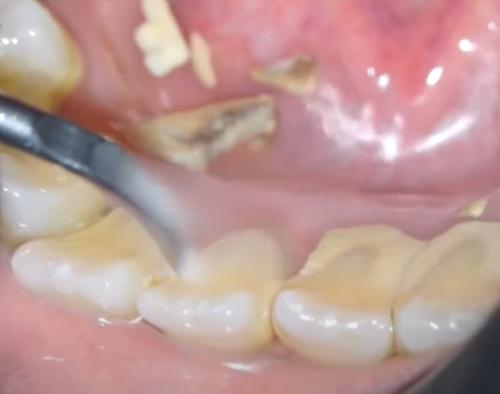

적절한 치아 위생을 실천하지 않으면 박테리아가 플라그 라고 하는 끈적끈적한 막으로 치아에 번식합니다. 플라그는 정기적으로 제거하지 않으면 결석이라고도 하는 치석으로 굳어집니다.

이것은 잇몸 라인 아래와 위의 단단하고 다공성인 물질입니다. 도달하기 어려운 부위와 치조골은 치석 축적이 발생할 위험이 더 큽니다. 치석이 쌓이면 굳어 일반 칫솔로는 더 이상 제거할 수 없습니다.

치료하지 않고 방치하면 그 단단한 물질 아래에서 일어나는 일이 치아에 심각한 손상을 줄 수 있습니다.

치석 축적은 충치 와 잇몸 후퇴를 직접적으로 유발합니다.

치아에 치석이 보인다면 박테리아가 끊임없이 법랑질을 먹고 있다는 뜻입니다. 그리고 당신은 그것을 닦거나 긁어낼 수 없습니다. 이는 치석이 제거될 때까지 손상이 계속 발생한다는 것을 의미합니다.